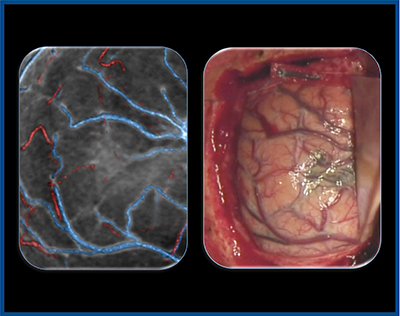

症例1は,80歳,女性,左前頭葉膠芽腫である。従来CTとAquilion Precisionの3D-CTAを比較したところ,動脈・静脈共にAquilion Precisionの方が脳表まで細い血管を描出できており,腫瘍との位置関係の把握に有用であった(図1)。

実際の手術の画像と比較しても,腫瘍周囲の血管の位置は術前の3D-CTA画像と一致していた(図2)。腫瘍の最も奥に走行している動脈(callosomarginal artery:)も同定されていたため,術前計画どおりに,この動脈まで腫瘍を摘出し,虚血を生じずに全摘出することができた。

図1 症例1:左前頭葉膠芽腫の術前3D-CTA(静脈)

図2 症例1:術前3D-CTAと手術画像の比較